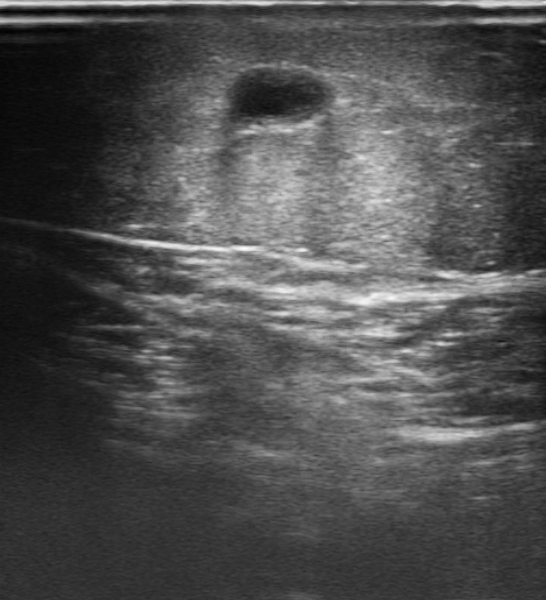

Buen estado general. Consciente y orientado en las 3 esferas. Bien perfundido. Eupneico en reposo. Auscultación cardiopulmonar: rítmica con murmullo vesicular conservado. En cara interna de miembro inferior izquierdo, zona eritematosa y ligeramente edematosa con palpación de trayecto endurecido de territorio de vena safena interna. Varices bilaterales (Imagen 1).

Ecografía de miembro inferior izquierdo: contenido hiperecogénico en todo el trayecto de la vena safena interna, no compresible. Sistema venoso profundo permeable sin datos de TVP (Imagen 2,3,4).